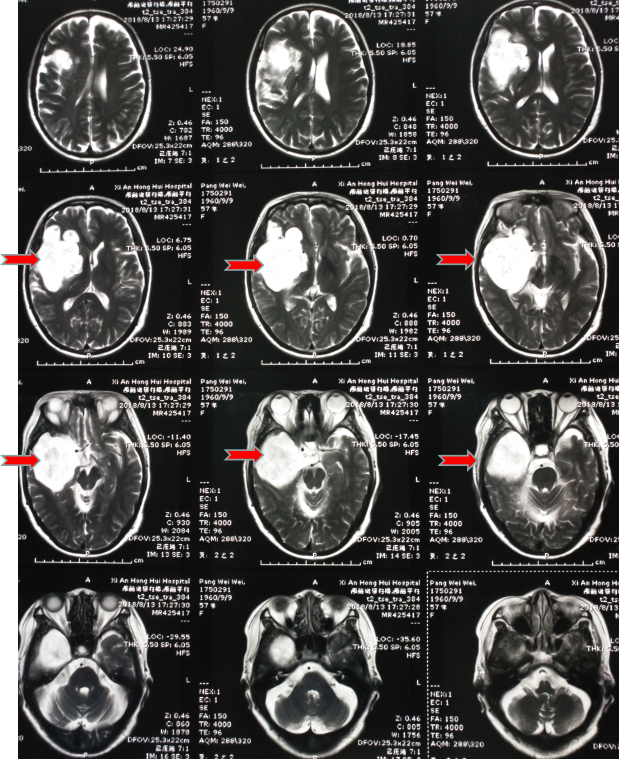

第二天趕緊到醫(yī)院看了一下,醫(yī)生說這是癲癇,隨后給她開了“丙戊酸鈉”長期口服,用藥后仍然每年有1-2次發(fā)作,大多是在晚上,有時(shí)即使沒有發(fā)生四肢抽搐,但有一種異樣的感覺。雖然這兩年很少發(fā)作了,但異樣感覺一直存在。今年她順利退休了,但教師的職業(yè)病——頸椎病卻讓他頸肩部以及上肢經(jīng)常麻木酸困,所以查了一下磁共振,確實(shí)存在頸椎病,但不需要手術(shù),只需保守治療即可。但意外的是發(fā)現(xiàn)了腦子里面長了個(gè)瘤子,大小約7厘米。

頭部磁共振提示腫瘤大小約7cm

一看片子,確認(rèn)是良性腫瘤,準(zhǔn)確點(diǎn)說應(yīng)該是一種叫做表皮樣囊腫的腫瘤,生長時(shí)間比較長,所以在早期很難發(fā)覺,經(jīng)常是在偶爾查頭部CT或者磁共振時(shí)發(fā)現(xiàn)。我給她說,這就是一直困擾她幾十年的病根所在,只要將它切除,她的癲癇和異樣感會(huì)逐漸消退,否則,隨著腫瘤增大,不僅會(huì)癲癇反復(fù)發(fā)作,而且會(huì)影響其他神經(jīng)功能??紤]再三,最終她還是選擇手術(shù)治療。

顱內(nèi)膽脂瘤的發(fā)病率為全腦腫瘤的0.5-1.8%??蔀槎喟l(fā),大小由幾毫米至數(shù)厘米不等。顱內(nèi)膽脂瘤目前認(rèn)為系胚胎期(妊娠3-5周)神經(jīng)管閉合時(shí)混入了外胚層成分所導(dǎo)致。沒有遺傳易感性,沒有易感基因,它的發(fā)病跟孕期孕婦營養(yǎng)不足或受到有毒物質(zhì)輻射有關(guān),導(dǎo)致胎兒的神經(jīng)管不能正常形成;顱內(nèi)膽脂瘤好發(fā)于鞍區(qū)、顱中窩和后顱窩,發(fā)生在后顱窩,壓住了面神經(jīng)和位聽神經(jīng),就會(huì)出現(xiàn)聽力下降、面部癱瘓,壓迫三叉神經(jīng),會(huì)出現(xiàn)繼發(fā)性三叉神經(jīng)痛,如壓迫后組顱神經(jīng),會(huì)產(chǎn)生飲水嗆咳和咽部麻痹癥狀,腫瘤在顱中窩,壓迫動(dòng)眼神經(jīng)會(huì)產(chǎn)生眼球活動(dòng)障礙、眼瞼下垂,鞍區(qū)的顱內(nèi)膽脂瘤,如在視丘下部,會(huì)導(dǎo)致病人意識(shí)朦朧、模煳,產(chǎn)生在垂體,會(huì)造成女性月經(jīng)失調(diào),男女不孕不育,電解質(zhì)紊亂會(huì)造成多飲、多尿或視力減退;顱內(nèi)膽脂瘤惡變幾率非常小,但如果不及時(shí)干預(yù),腫瘤長大后會(huì)破裂,會(huì)造成腦組織炎癥,導(dǎo)致病人顱內(nèi)壓增高,甚至唿吸驟停;顱內(nèi)膽脂瘤發(fā)病率占顱內(nèi)腫瘤的1.5%-2%,男女發(fā)病比例為1.25:1,一般多在20-40歲產(chǎn)生癥狀,跟地域和飲食、生活習(xí)慣等都沒有關(guān)系。顱內(nèi)膽脂瘤的治療一般以手術(shù)治療為主,宜手術(shù)切除,然而因腫瘤與血管粘連緊密,國內(nèi)外很多專家認(rèn)為完全切除是不明智的,且應(yīng)避免,以免致殘或死亡,術(shù)后復(fù)發(fā)時(shí)間一般為數(shù)年,長者可達(dá)十幾年,術(shù)后復(fù)發(fā)率為5%。所以術(shù)后應(yīng)定期到醫(yī)院復(fù)查,如果復(fù)發(fā)可以再次手術(shù),預(yù)后還是比較理想的。